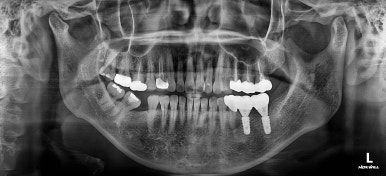

초진 시 X-ray 사진인데요.

이가 없는 뒤쪽 치아가 앞으로 쓰러져있고요. 맨 뒤에 사랑니까지 앞으로 쓰러져있네요.

이대로 임플란트도 못할 뿐더러 이대로 계속 지낸다면 쓰러진 치아에 계속 힘이 가해지니 치아 수명에 굉장히 안좋아요.